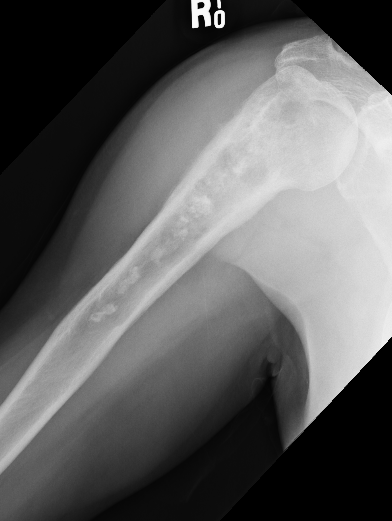

X-ray

Lytic lesion with punctate or spotty calcification

Worrisome features

- large > 5cm

- endosteal scalloping is hallmark of chondrosarcoma

Large calcification with endosteal scalloping humerus

Large calcified lesion with endosteal scalloping